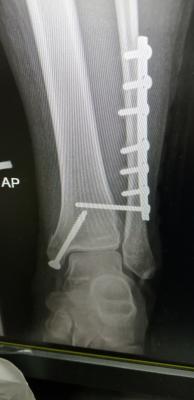

Mai scare me leg. My scan results are out. Ligament tendon all good. Just bone broken and one part dislocated. Broken part all screws. Dislocated, screwed back to strengthen.

just wait untill fractured heal...for time being slowly get range movement ankle and partially weight bearing if more than 6 week..and ostechondral injury cannot be seen in xray or ct scan..even sometimes mri also can be miss..u definitely have it as your medial malleolus fractured involving ankle joint which have cartilage over there..Mai scare me leg. My scan results are out. Ligament tendon all good. Just bone broken and one part dislocated. Broken part all screws. Dislocated, screwed back to strengthen.